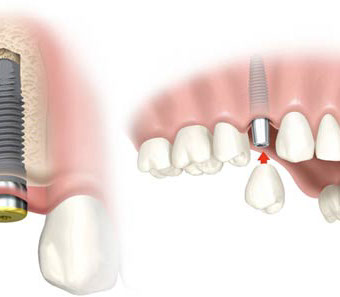

sostituire singoli denti, senza coinvolgere i denti vicini, così come avveniva in passato quando non esisteva alternativa alla realizzazione di un Ponte.

Gli impianti da noi utilizzati sono a forma di vite, hanno un diametro da 3,5 a 6,0 mm e una lunghezza da 5 a 15 mm, approssimativamente, quindi, la dimensione di una radice naturale.